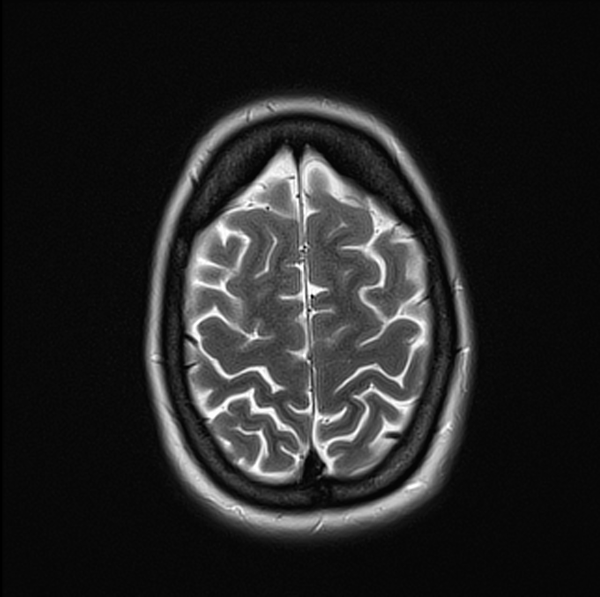

MRI Brain Anatomy 3T 3MM